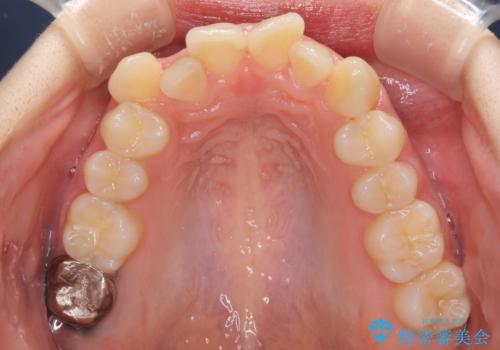

- 前歯のデコボコを気にして来院された患者様です。

本人は気づいていませんでしたが、下顎前歯が2本欠損しており、上下の歯列がアンバランスとなりデコボコになっていました。

上下のバランスを取るため、上顎左右第一小臼歯2本を抜歯し、ワイヤー矯正を行うこととしました。